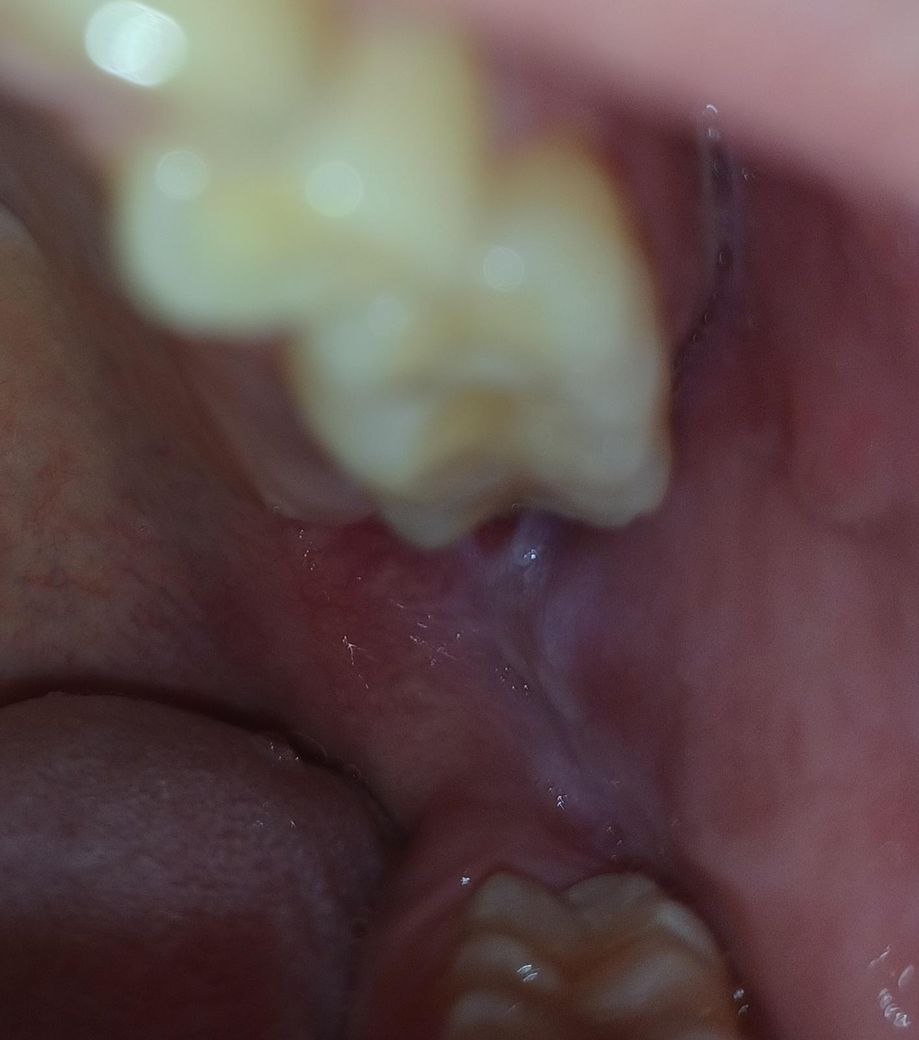

구내염인가요? 아니면 다른걸까요?

3일째인데 통증이 더 심해져서 확인해보니까 붉은색이 조금 보이던데 구내염일까요?

작년에는 구내염이 생겼을때는 저런식으로 붉은색은 안보였었는데 이것도 그냥 놔두면 1~2주면 괜찮아지겠죠?

구내염인가요? 아니면 다른걸까요? -> 사진상으론 구내염 양상 같습니다. 자극적인 음식 피하시고 1~2주 정도 증상 지켜보시죠

사진이 명확하진 않지만 단순 구내염일 가능성이 높아보입니다. 며칠 지나면 사라질겁니다.

사진에 보이는건 볼살이 치아에 씹혀서 생긴 상처 같은겁니다. 사랑니 때문에 그럴수도 잇으니 치과에 가셔서 검진을 받아보세요.